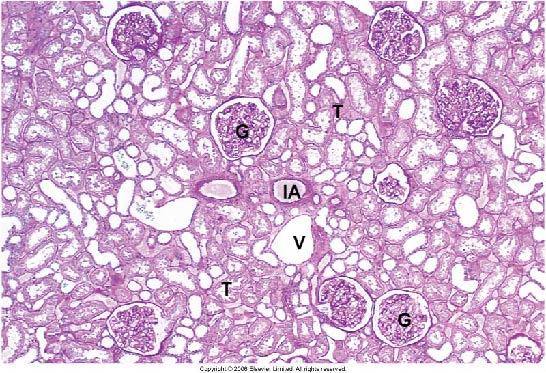

Identify the structures labeled ‘G’ in this H&E section of the renal cortex

glomeruli

Identify the structures indicated by the arrows in this cross-section of the kidney.

Renal Corpuscles

Renal corpuscles are a distinctive feature of kidney cortex.